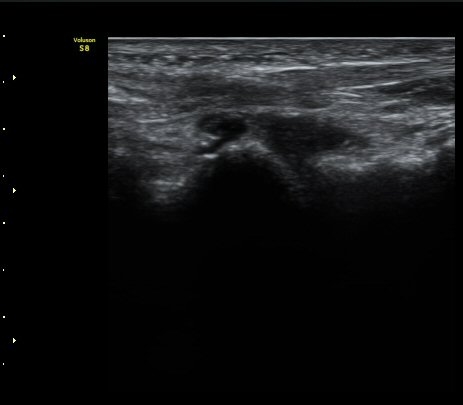

ÃÊÀ½ÆÄ °Ë»ç

Á¾°ñÀÔ¹æ°ñÀδëÀÇ Á¾´Ü¸é°Ë»ç¿¡¼­ ÀδëÀÇ Á¾°ñ ºÎÂøºÎ ÆÄ¿­ÀÌ °üÂûµÊ(»çÁø 1, 2, 3).

Á¾°ñÀÔ¹æ°ñÀÎ´ë ¿ÜÃø Á¾´Ü¸é°Ë»ç¿¡¼­ ¼ö¾×Àú·ù°¡ °üÂûµÊ(»çÁø 6, 7).

ÃÊÀ½ÆÄÀ¯µµÇÏ Á¾°ñÀÔ¹æ°ñ°ñ°üÀý ºÎÇϰ˻翡¼­ °í³ªÀýÀÇ ºÒ¾ÈÁ¤ÀÌ °üÂûµÊ(÷ºÎÆÄÀÏ)